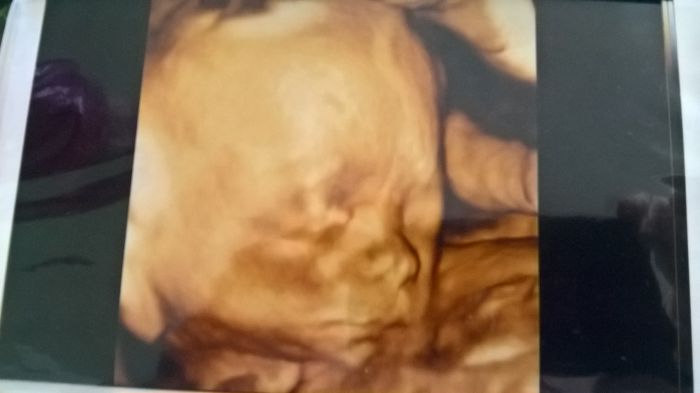

holky vám ostatním držím moc palce. Jinak irco těhotné se cítit nemusíš. Ja se cítím netehotna stale a to uz jsem 21tt. Jinak přikládám foto našeho chlapecka. A přeji vám vsem taky takový štěstíčko.na me se usmálo skoro az po dvou a pul letech. Možná pomohl jakbuz jsem psala ten zázvor.jinak nechápu čím se stal zázrak. Jinak druhy screening mi dopadl dobre. Az na tu preeklampsii kterou mi hrozi riziko uz z prvního.